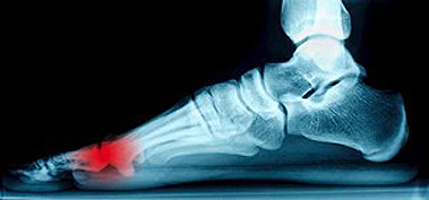

If you have consistent pain and discomfort in the heel of your foot, you may have a medical condition that is referred to as plantar fasciitis. It will typically target people who are active in running sports, or for those who stand for the majority of the day. This ailment is a result of inflammation that occurs in the long portion of tissue that runs along the bottom of the foot, which links the toes to the heel, and this is known as the plantar fascia. A common symptom of this ailment is severe heel pain, which may often be worse in the morning when the first steps are taken. Some patients have specific tendencies that may encourage the development of this condition, including being overweight, wearing shoes that do not fit correctly, or are born with flat feet or high arches. There are possible techniques that may offer moderate relief, and these may include performing proper foot stretches, resting your feet as often as possible, or wearing shoe inserts. If you have developed this condition, it’s suggested to speak with a podiatrist to understand what treatment options are correct for you.

Plantar fasciitis is a common foot condition that is often caused by a strain injury. If you are experiencing heel pain or symptoms of plantar fasciitis, contact Brent Harwood, DPM from Southeast Podiatry. Our doctor can provide the care you need to keep you pain-free and on your feet.

What Is Plantar Fasciitis?

Plantar fasciitis is one of the most common causes of heel pain. The plantar fascia is a ligament that connects your heel to the front of your foot. When this ligament becomes inflamed, plantar fasciitis is the result. If you have plantar fasciitis you will have a stabbing pain that usually occurs with your first steps in the morning. As the day progresses and you walk around more, this pain will start to disappear, but it will return after long periods of standing or sitting.

What Causes Plantar Fasciitis?

There are some risk factors that may make you more likely to develop plantar fasciitis compared to others. The condition most commonly affects adults between the ages of 40 and 60. It also tends to affect people who are obese because the extra pounds result in extra stress being placed on the plantar fascia.

Prevention

There are a variety of treatment options available for plantar fasciitis along with the pain that accompanies it. Additionally, physical therapy is a very important component in the treatment process. It is important that you meet with your podiatrist to determine which treatment option is best for you.